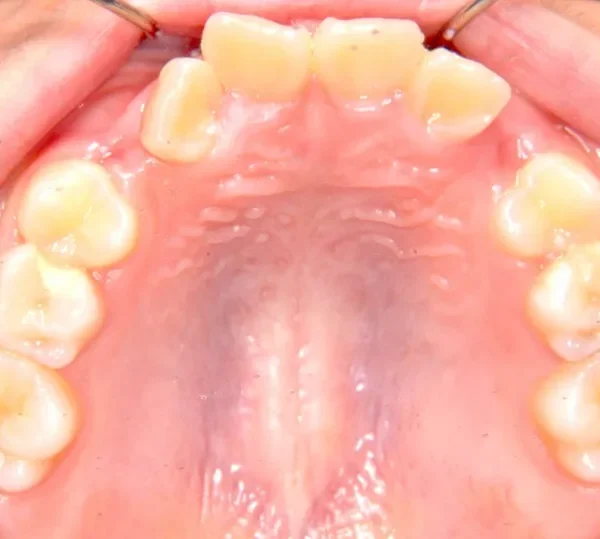

【子供の矯正(一期)】叢生・前歯がゆがんでいる・犬歯の生える隙間がない・9歳女児【M.O】

初診時年齢 小学校3年生 (女性) 主訴 前歯がゆがんでいる・犬歯の生える隙間がない

診断名 叢生 装置名

上下がガタガタで犬歯の生えるすきまがありません。

このままだと犬歯の生えるスペースがありません。放っておくと犬歯が上の位置からはえ、牙のようになってしまいます。

乳歯があるうちは上下オリジナル固定装置を利用し、永久歯が生えそろったらマルチブラケット装置を利用して治療しました。